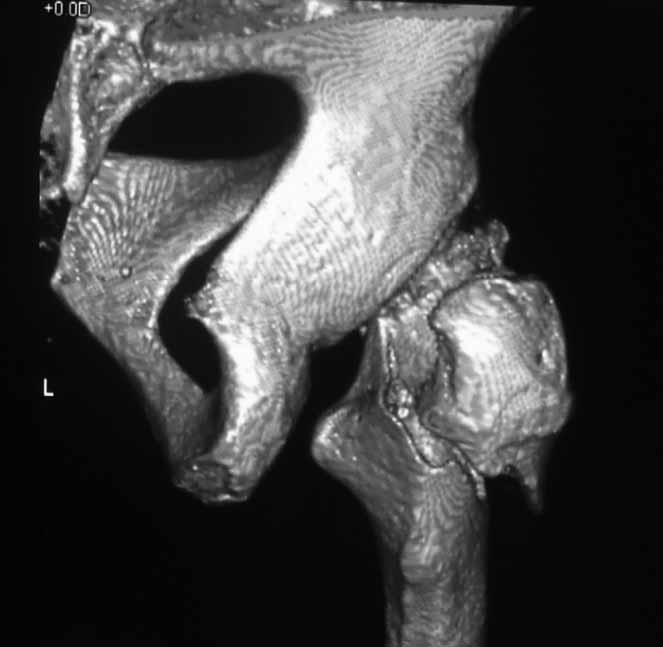

Пациентка 53 лет. ДТП 09.01.12: сочетанная травма: перелом 2-5 ребер справа, ушиб легких;

перелом обеих лонных костей без смещения; закрытый перелом проксимального конца правой

бедренной кости; открытый оскольчатый внутрисуставной перелом проксимальных концов

костей правой голени.

Бедро одномоментно делать не стал, не было уверенности в наличии перелома на уровне шейки. Во время операции смотрел тазобедренный сустав под ЭОПом,

головка неподвижна. После операции повторили КТ, стало очевидно, что имеется субкапитальный перелом. Что делать, остесинтез или протезирование? Если остеосинтез, то чем? Заранее благодарен за советы.